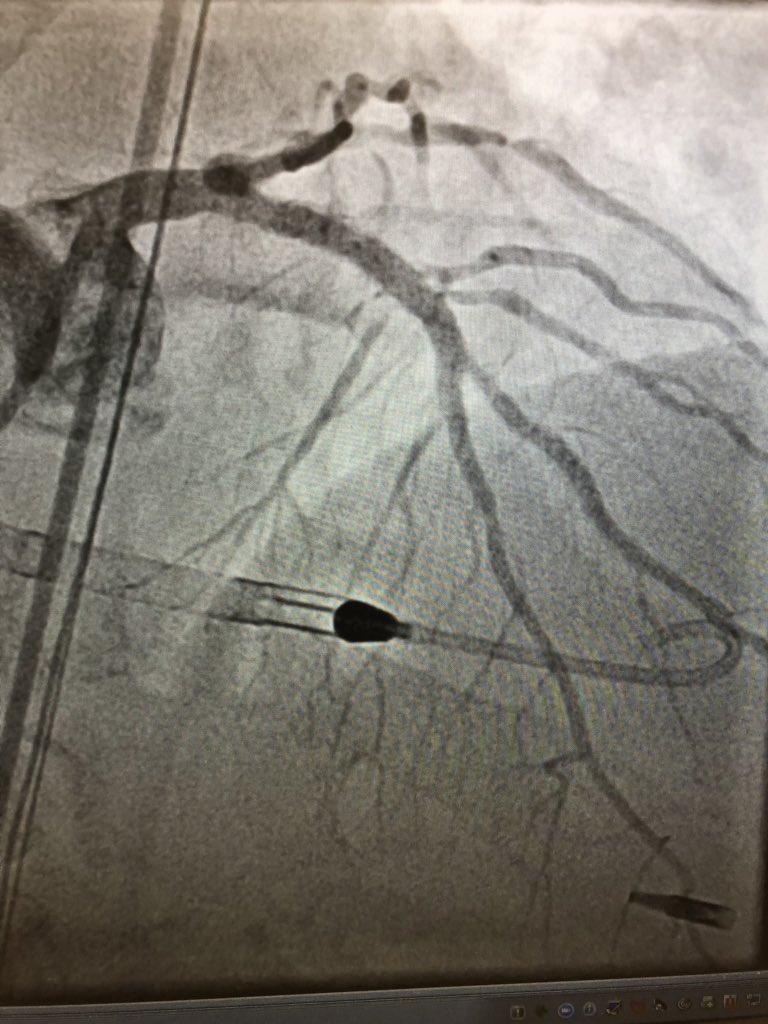

Always Angio w 4F #Micropuncture sheath before #Ax #Largeboreaccess @AntoniousAttall @payalkohlimd @sjgips @aelsab @Michel_CorbanMD @EmileMehanna @essadii @SamKMehta @fjsawaya @evhaddad @dimitri_zappi @gbiondizoccai @sbrugaletta @twj1974 @mmamas1973 @nickaram @crfheart @TCTMD